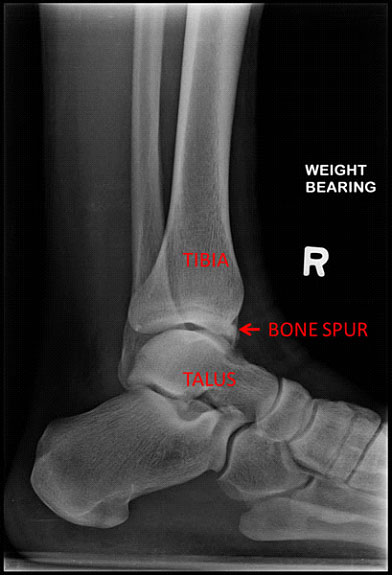

Ankle bone spurs is a condition that occurs when an extra bone grows in front of the ankle joint. It usually develops just in front of the ankle joint at the point where the leg bone ( the tibia ) meets the ankle bone ( the talus ). This condition is also known as footballer’s ankle, athlete’s ankle, or medically as anterior ankle ‘bony’ impingement syndrome.

The bone spurs can either occur from the tibia, the talus or both. When the foot is moved upwards, the bone spurs knock on each other, resulting in severe pain and inflammation over the front of the ankle. There is a sensation of pinching or impingement of the tendons, ligaments or the capsule.

The diagnosis of ankle bone spurs is usually made with an X-ray. Other imaging tests like the MRI (Magnetic Resonance Imaging) and CT (Computed Tomography) scan may be used to confirm the severity of the diagnosis and ensure there are no other pain-causing problems in the ankle joint. (such as cartilage defects or ligament tears ).